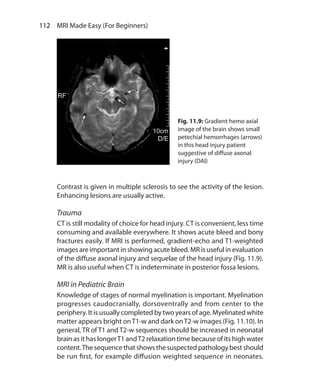

Sacroiliitis 118f

Saddle coil 31f

Safety issues 96, 126

Saturation band 56, 74

Selection of VOI 162

Shading artifact 82f